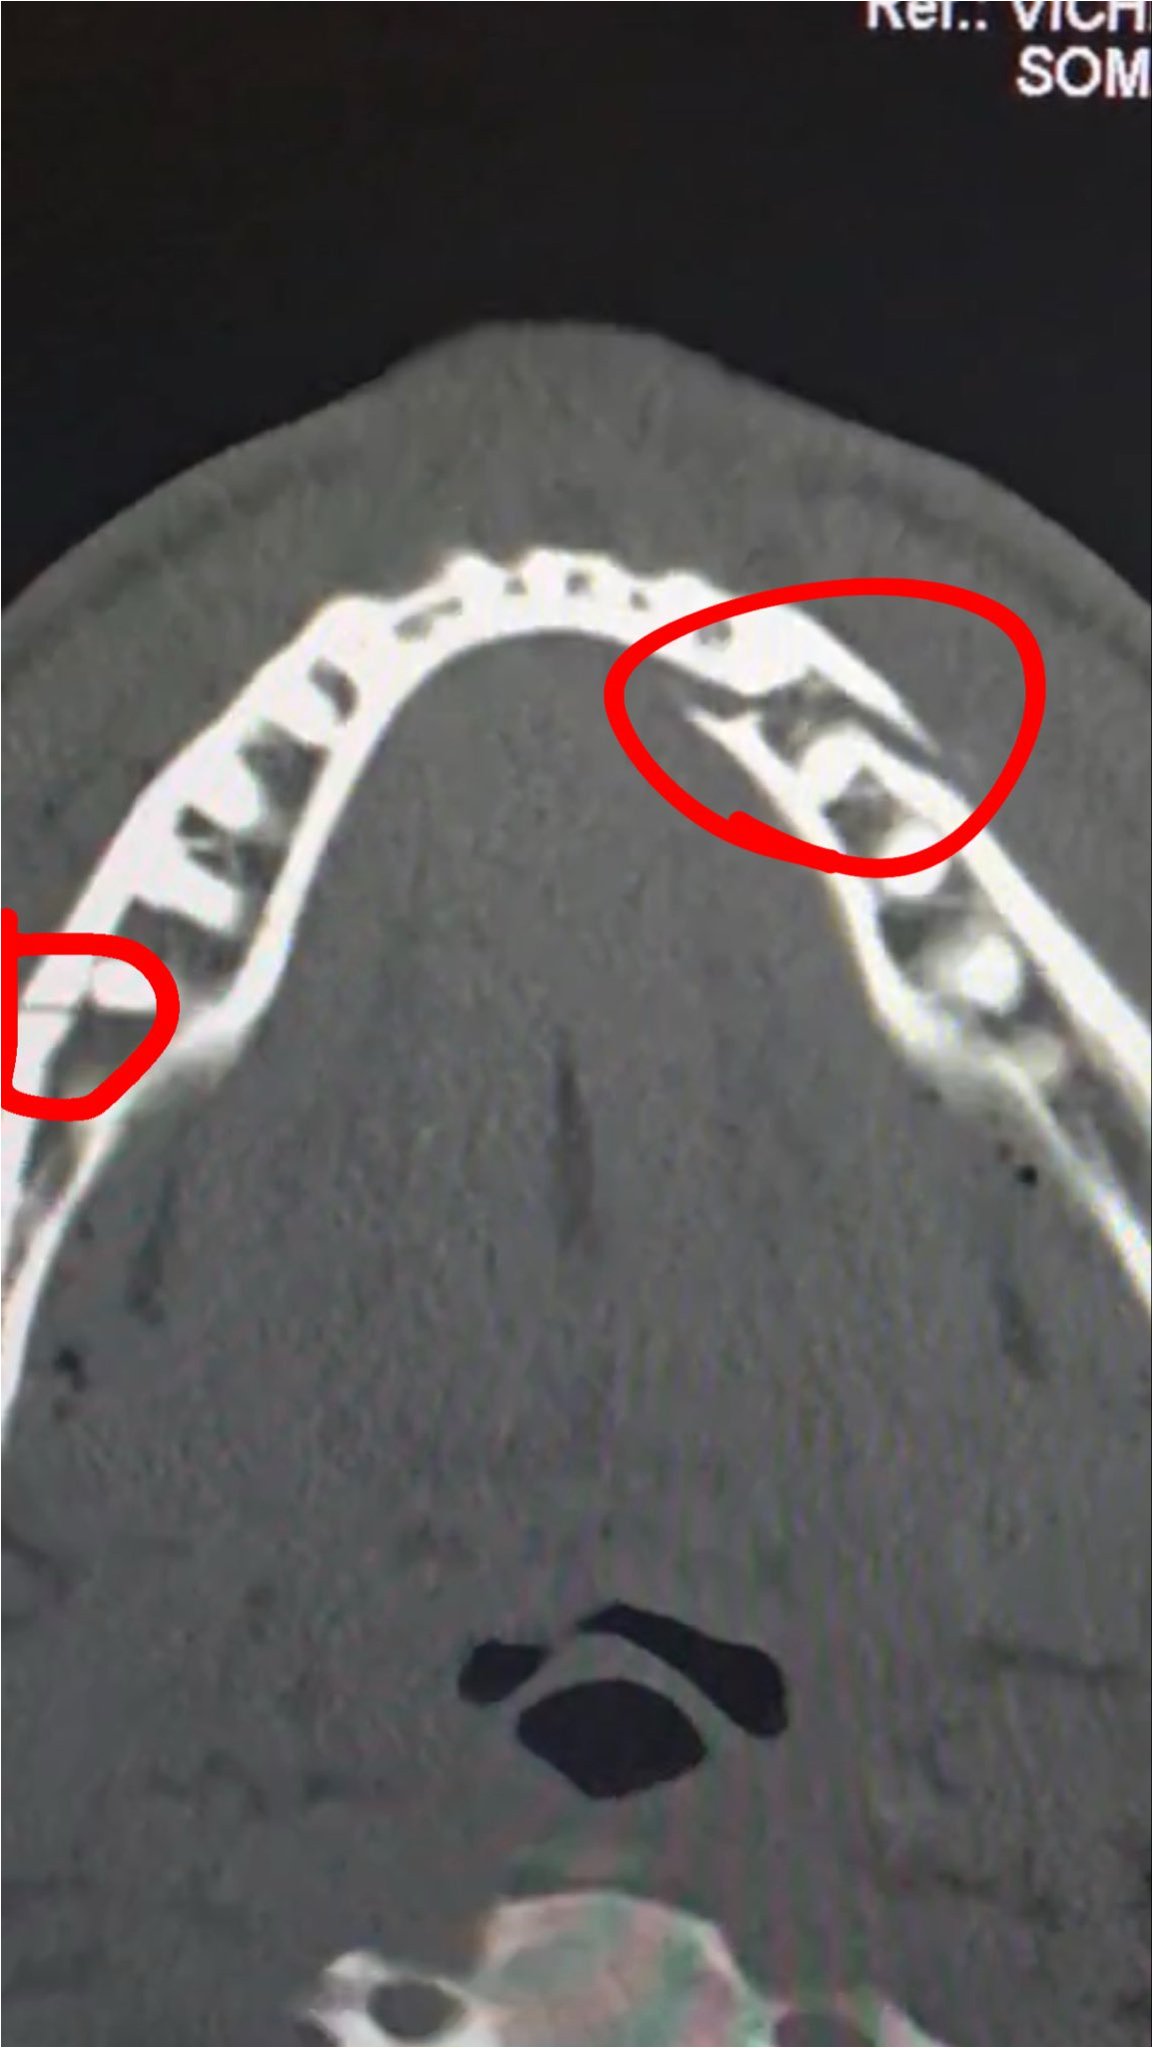

Q.폴의 턱뼈 부상은 얼마나 심각한가요?

A.폴은 턱뼈가 두 군데 부러지는 부상을 입었습니다. 하지만 그의 SNS를 통해 공개된 사진에서도 긍정적인 모습을 보여주며, 팬들을 안심시켰습니다.